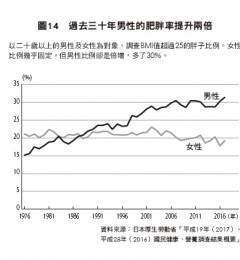

在死于心脏疾病的癌症患者中男性占60%,而在年龄分布上70岁以上者死亡率较高。死于心脏病的癌症患者最常见的原位癌分别为:前列腺癌(22.1%)、结肠癌(15.3%)、乳癌(12%)、肺癌(9.6%)、膀胱癌(7.4%)。膀胱癌的心脏病死亡率最高(8.4%)。有53.4%接受手术。

而预测癌症患者死于心脏病的因子包括:男性、诊断时已届高龄、接受手术、罹患原位癌乳癌及肺癌。